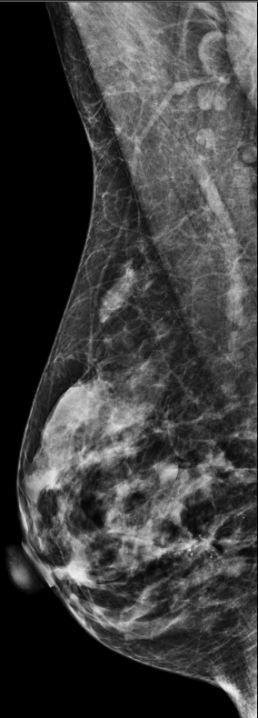

MAMMOGRAPHIE BILATÉRALE EN 3D.

Les seins sont hétérogènes en densité. Il existe un groupe irrégulier de calcifications du sein médian droit. Il y a aussi une zone de distorsion architecturale potentielle immédiatement postérieure aux calcifications sur la droite. Dans le sein gauche, il y a une densité nodulaire bien circonscrite latéralement, kyste possible. Il y a une densité nodulaire micro lobulée dans le sein gauche

RÉSULTATS DE LA MAMMOGRAPHIE : Il y a une masse bien circonscrite de 10 mm dans l’extérieur du sein gauche, probablement un kyste. Il existe un parenchyme mammaire asymétrique inférieur et médian, précédemment évalué et démontré par le tissu mammaire normal. Il existe de nombreuses calcifications arrondies légèrement irrégulières de taille rétrécissante dans le sein médial droit. Les calcifications sont situées principalement à l’avant; il y a une extension postérieure et latérale des calcifications sur une longueur de 4 cm. Il y a aussi une distorsion architecturale associée. Il peut y avoir une masse présente.

RÉSULTATS DE L’ÉCHOGRAPHIE : L’intérieur du sein droit, à 9 h, à 8 cm du mamelon, présente une masse kystique allongée de 1,7 x 1 0,6 à 0,5 cm, mais pas de masse solide. En position 2:30, à 5 cm du mamelon, il y a une masse solide hypoéchographique irrégulière de 1,0 x 0,6 x 1,4 cm avec une vascularité interne. À la position 3:00, 4 à 5 cm du mamelon, il y a une masse hypo échographique marginale irrégulière de 2,5 x 1,7 x 0,8 cm contenant des calcifications et une vascularité interne. Les masses sont à 2,3 cm l’une de l’autre.